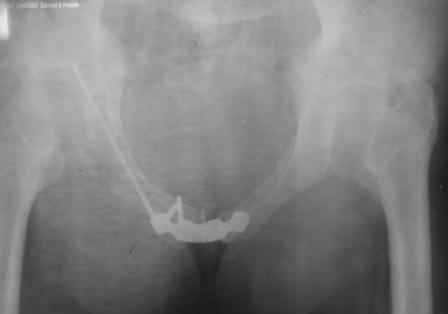

положение и точка введения винта, при фиксации перелома горизонтальной ветви лонной кости и возможно acetabulum, определяется её анатомией. Корректная позиция и точка введения в приложенных картинках из руководства по внутреннему остеосинтезу.

С Уважением А.Миронов